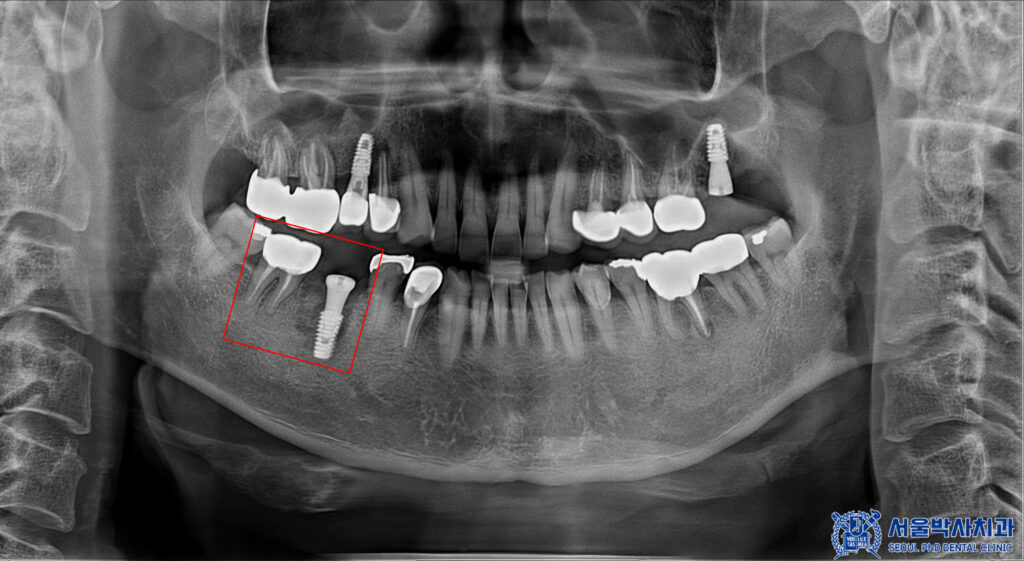

이번에 내원하신 환자분은

왼쪽 위 어금니 없이 지내신지 꽤 되셨고

전체적인 검진도 받아보기 위해

본원에 내원해 주셨습니다.

확인해 보니,

왼쪽 위 어금니의 상실이 있었고

사랑니도 있었습니다.

또한 오른쪽 아래

첫번째 큰 어금니 뿌리 끝으로

염증이 크게 잡혀있는 것을

확인 할 수 있었습니다.